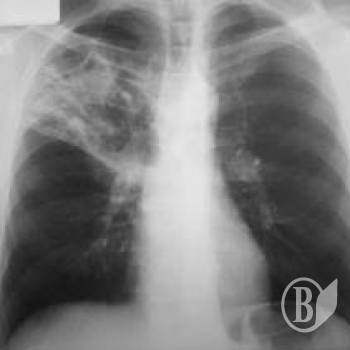

Захворюваність серед постраждалих у 2012р. становила 71,8 тис. випадків уперше встановлених діагнозів на кожні 100 тис. осіб, що перебували на обліку. Найбільш розповсюдженими були хвороби органів дихання (36,1 тис. випадків), системи кровообігу (5,6 тис.), шкіри і підшкірної клітковини (4,3 тис.), кістково-м’язової системи та сполучної тканини (4,0 тис.), сечостатевої системи (3,5 тис.) тощо.

За даними обласного центру радіаційного захисту та оздоровлення населення, у медичних закладах області системи МОЗ на кінець 2012р. під наглядом перебували 8,8 тис. ліквідаторів наслідків аварії на ЧАЕС (І група первинного обліку), 1,4 тис. осіб, евакуйованих із зони дії радіації (ІІ група), 56,6 тис. осіб, які проживали або проживають на територіях, що підлягають нагляду (ІІІ група), 15,0 тис. дітей, батьки яких належать до названих вище категорій (ІV група) та 332 дитини, народжені від осіб IV групи обліку.

Усі вони майже повністю (від 88,9% до 100%) пройшли медичний огляд. Однак здоровими визнано лише 1,1% оглянутих лікарями ліквідаторів, 2,2% – евакуйованих, 6,4% – осіб ІІІ групи обліку, 14,6% – ІV групи та 38,6% дітей, які народилися від осіб IV групи обліку.